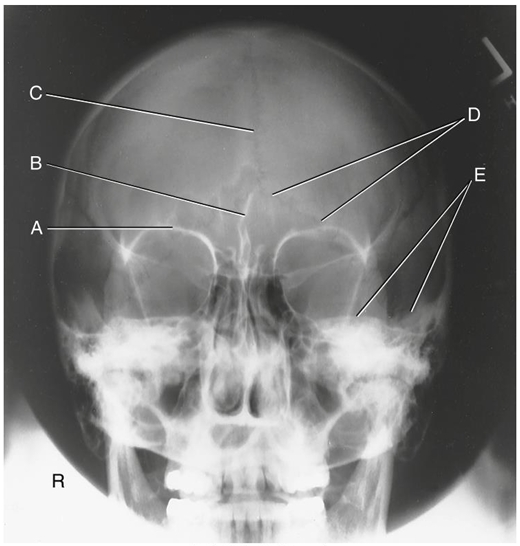

What is A?

supraorbital margin of right orbit (SOM)

What is B?

crista galli of ethmoid

What is C?

sagittal suture (post skull)

What is D?

lambdoidal suture (post skull)

What is E?

petrous ridges